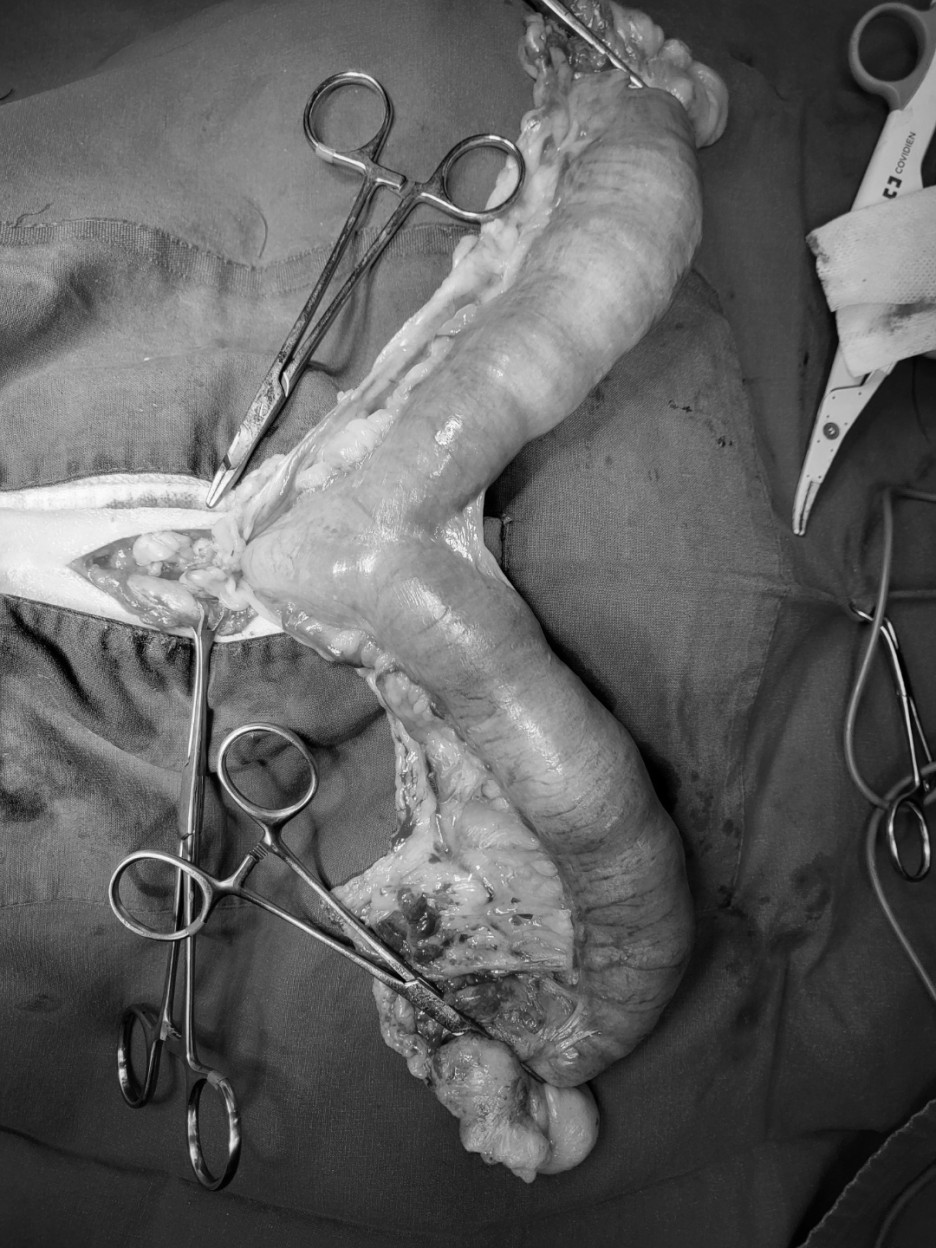

제거한 자궁과 난소

자궁체 절제 → 제거한 자궁 → 자궁내 혈액성 농성 삼출물

강아지의 자궁축농증이 있는 자궁은 이렇게 쌓인 고름처럼 사진처럼 팽창하게 된다.

이 환자의 자궁 내에는 혈액성 농성 삼출물로 가득 차 있었습니다.